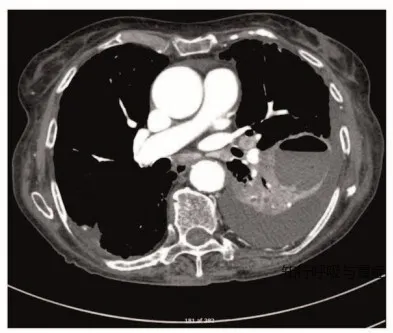

2)评估:胸部X线和CT扫描有助于诊断肺脓肿。

肺脓肿的CT扫描

肺脓肿与肺部囊性病变(如肺内支气管囊肿、肺隔离症或继发性感染的肺气肿性大疱)的鉴别有时较为困难。然而,病变的部位和临床表现通常能为诊断提供指导。局部性胸膜脓肿可通过CT扫描或超声进行区分。其中气-液平面的影像学表现也可见于肺部包虫囊肿。

肺包虫囊肿可见气液平面